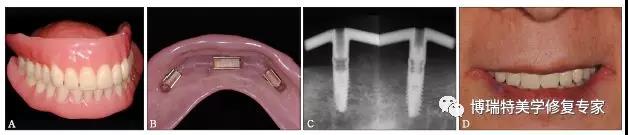

再于患者口内试戴检查,制作杆卡及全口义齿。采用计算机辅助设计与制作(computer aided design/computer aided manufacturing,CAD/CAM)技术切削纯钛杆(图6)。

图6 计算机辅助设计杆的形状与位置 A:左侧观;B:右侧观

口内试戴杆卡及全口义齿(图7A、B),拍摄X线片检查杆与种植体平台的密合性(passive fit)(图7C),将基台种植体连接并加力至25 N·cm,完成最终修复(图7D)。

图7 最终修复效果 A:全口义齿;B:固位卡组织面观;C:X线片检查杆卡的被动就位,左侧未旋入基台螺丝,右侧旋入基台螺丝;D:正面微笑照